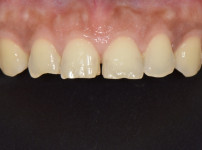

상악전치부 심미보철

최OO님/치료기간:2주/상악전치...